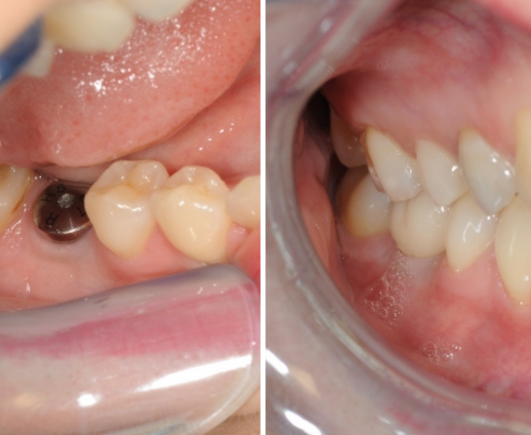

PRZED

PO

Przed i Po Naszych Klientów